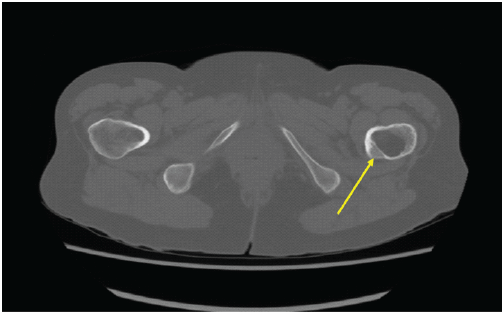

A 64-year-old female presented following a mechanical fall at work, reporting bilateral hip pain, more pronounced on the left side. The patient had no history of hip pain before the fall. Clinical examination demonstrated a preserved range of motion in both hips, with discomfort on weight bearing but no focal neurological deficit. Initial anteroposterior pelvic radiography demonstrated no acute fracture, but revealed a well-defined lucent lesion in the proximal left femur (Fig. 1). A computed tomography (CT) scan of the pelvis was subsequently performed to exclude an occult fracture. CT confirmed an elongated intramedullary lucent lesion within the proximal left femoral metaphysis, characterized by sclerotic margins without cortical destruction, endosteal scalloping, or an associated soft-tissue mass, suggesting a non-aggressive process (Fig. 2 and 3).

Figure 2: Axial computed tomography image at the level of the proximal femur showing a centrally located intramedullary lucent lesion with preserved cortical integrity and absence of endosteal scalloping or periosteal reaction (arrow).